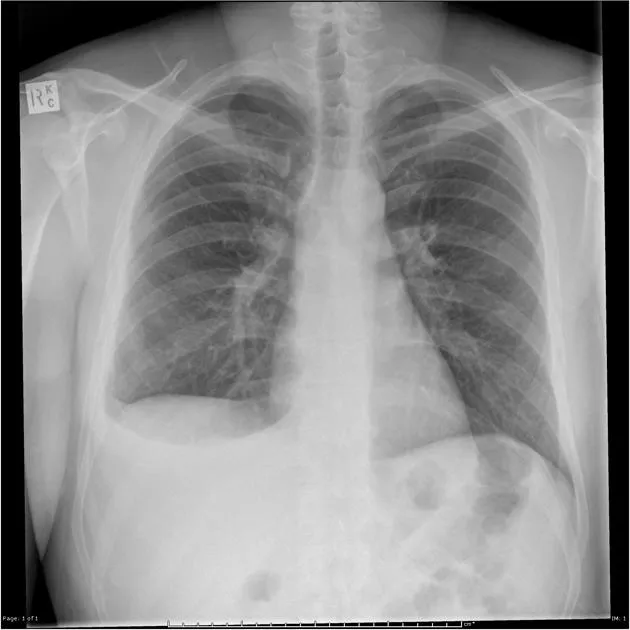

Air accumulation in the pleural space causes partial or complete lung collapse. Presents with acute dyspnea, pleuritic chest pain, and ↓ breath sounds.

⭐ Tension Pneumothorax: Characterized by mediastinal and tracheal deviation away from the affected side, hypotension, and JVD. Requires immediate needle decompression in the 2nd intercostal space, midclavicular line, followed by chest tube insertion.